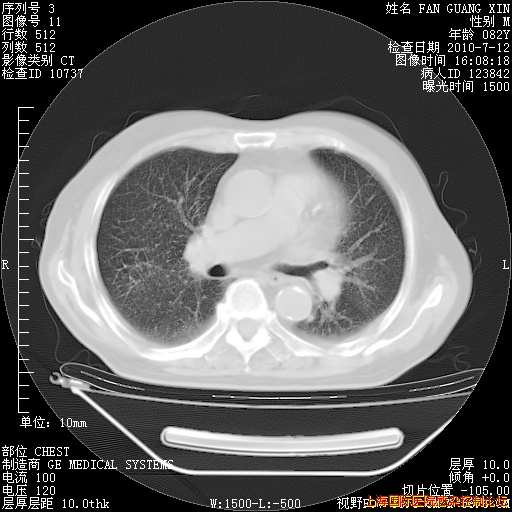

补发6月12日肺部CT肺窗

今天复查CT

今天CT

整整相隔30天的肺部CT好像有所好转啊。甲强龙减量第3天,需要观察体温。

海管,自昨日你和我通完话后,不知您岳父消化道症状有无缓解?体温怎样?阅读7.12日胸部ct,个人认为目前激素治疗是有效的,甲强龙减量是适宜的。因在抗痨治疗,需密切观察肝功、肾功能和血常规。不过,老年、长期住院和大量使用激素,很担心菌群失调发生